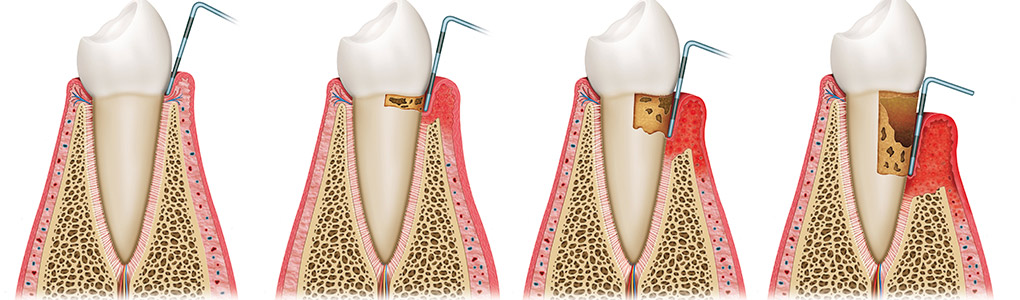

健康的牙齒跟牙齦幾乎是緊密貼合的。牙醫師會使用有刻度的牙周探針,針對每一顆牙齒進行探測檢查,沿著牙面弧度提放式行走,紀錄每一顆牙齒的牙周狀態。健康的牙周狀態,以探針探測,深度介於1-3mm之間,通常不會有滲血狀態出現,而是否有「探測時出血」,是牙齦健康的重要指標之一。當結石形成,發炎的現象越來越嚴重,患有牙周病的牙齒,探測深度會大於3mm,也就是進一步形成牙周囊袋,並且會逐漸加深。由於牙周病菌具有厭氧特性,氧氣較少的牙周囊袋正好成為孕育牙周病的溫床。牙周病菌不斷增生,散發出毒素,並且引發宿主免疫反應,造成齒槽骨吸收。當齒槽骨高度下降,便降低了對牙齒的支持力。如果置之不理、沒有妥善治療,經常導致牙齒喪失或需要拔除。

牙周病的發展階段

牙周病有別於其他牙齒的問題,經常在不自覺的情況下悄悄地發生。

如果以為牙齒或牙齦沒有疼痛就不需要治療,則可能使牙周病在不知不覺中演變到無法挽回的地步。健保給付半年定期洗牙,目的在於及早發現病灶,牙齦炎或輕度牙周病可以藉由簡單的防治,達到極好的效果。

了解與牙周病的發展,也可幫助民眾做簡單的自我檢查,以便早期發現、早期治療。健康的牙齦組織為但淡粉紅色,牙齦結實。一旦牙菌斑累積,初期會引發牙齦炎,此時牙齦外觀紅腫,刷牙時牙齦會出血。當牙齦發炎沒有即時控制治療,牙齦炎將發展至牙周病,病患會發現牙齦明顯退縮、牙縫越來越大、牙齒開始對冷熱酸痛敏感、口臭、牙齒搖動,咀嚼時不如以往紮實有力,甚至會有疼痛感,嚴重者口內會出現化膿現象。